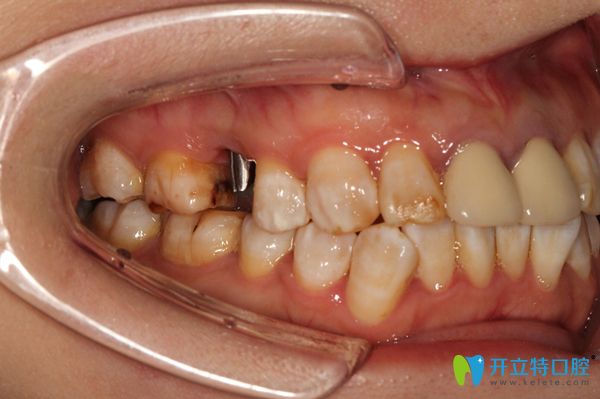

錢女士今年30多歲了,她的上頜右側(cè)牙齒在外力的作用下,缺失了一顆牙齒,不僅僅有點(diǎn)影響美觀,更重要的影響正常的咀嚼,還老塞牙。

上頜右側(cè)牙齒缺失一顆圖示